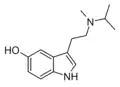

| 5-HO-MiPT | artificial | 5-OH | CH3 | CH(CH3)2 | 5-hydroxy-N-methyl-N-isopropyltryptamine | |